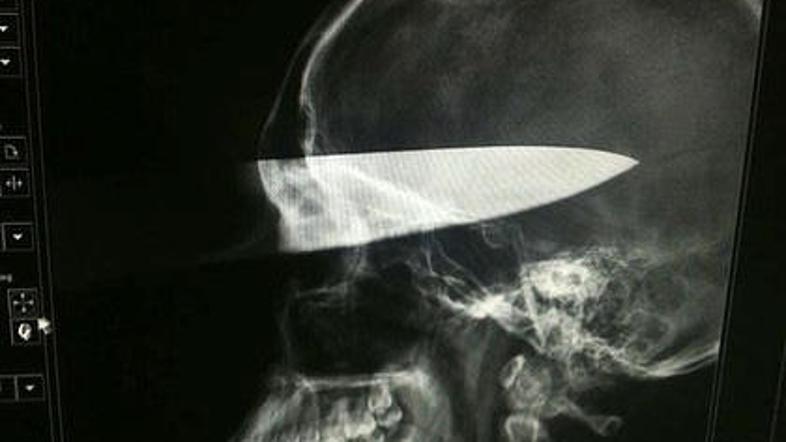

Rentgen je pokazal, kako globoko se je zaril nož. (Foto: smh.com) Žurnal24 main

Med pretepom mu je napadalec zabodel 30-centimetrski nož v obraz. Neverjetna sreča: nož zgrešil vse vitalne dele, mladenič preživel brez posledic.

Alexov kirurg je pojasnil, da je nož zgrešil oko, lobanjo, glavne žile in živce. ''Imel je neverjetno srečo,'' pravi zdravnik.